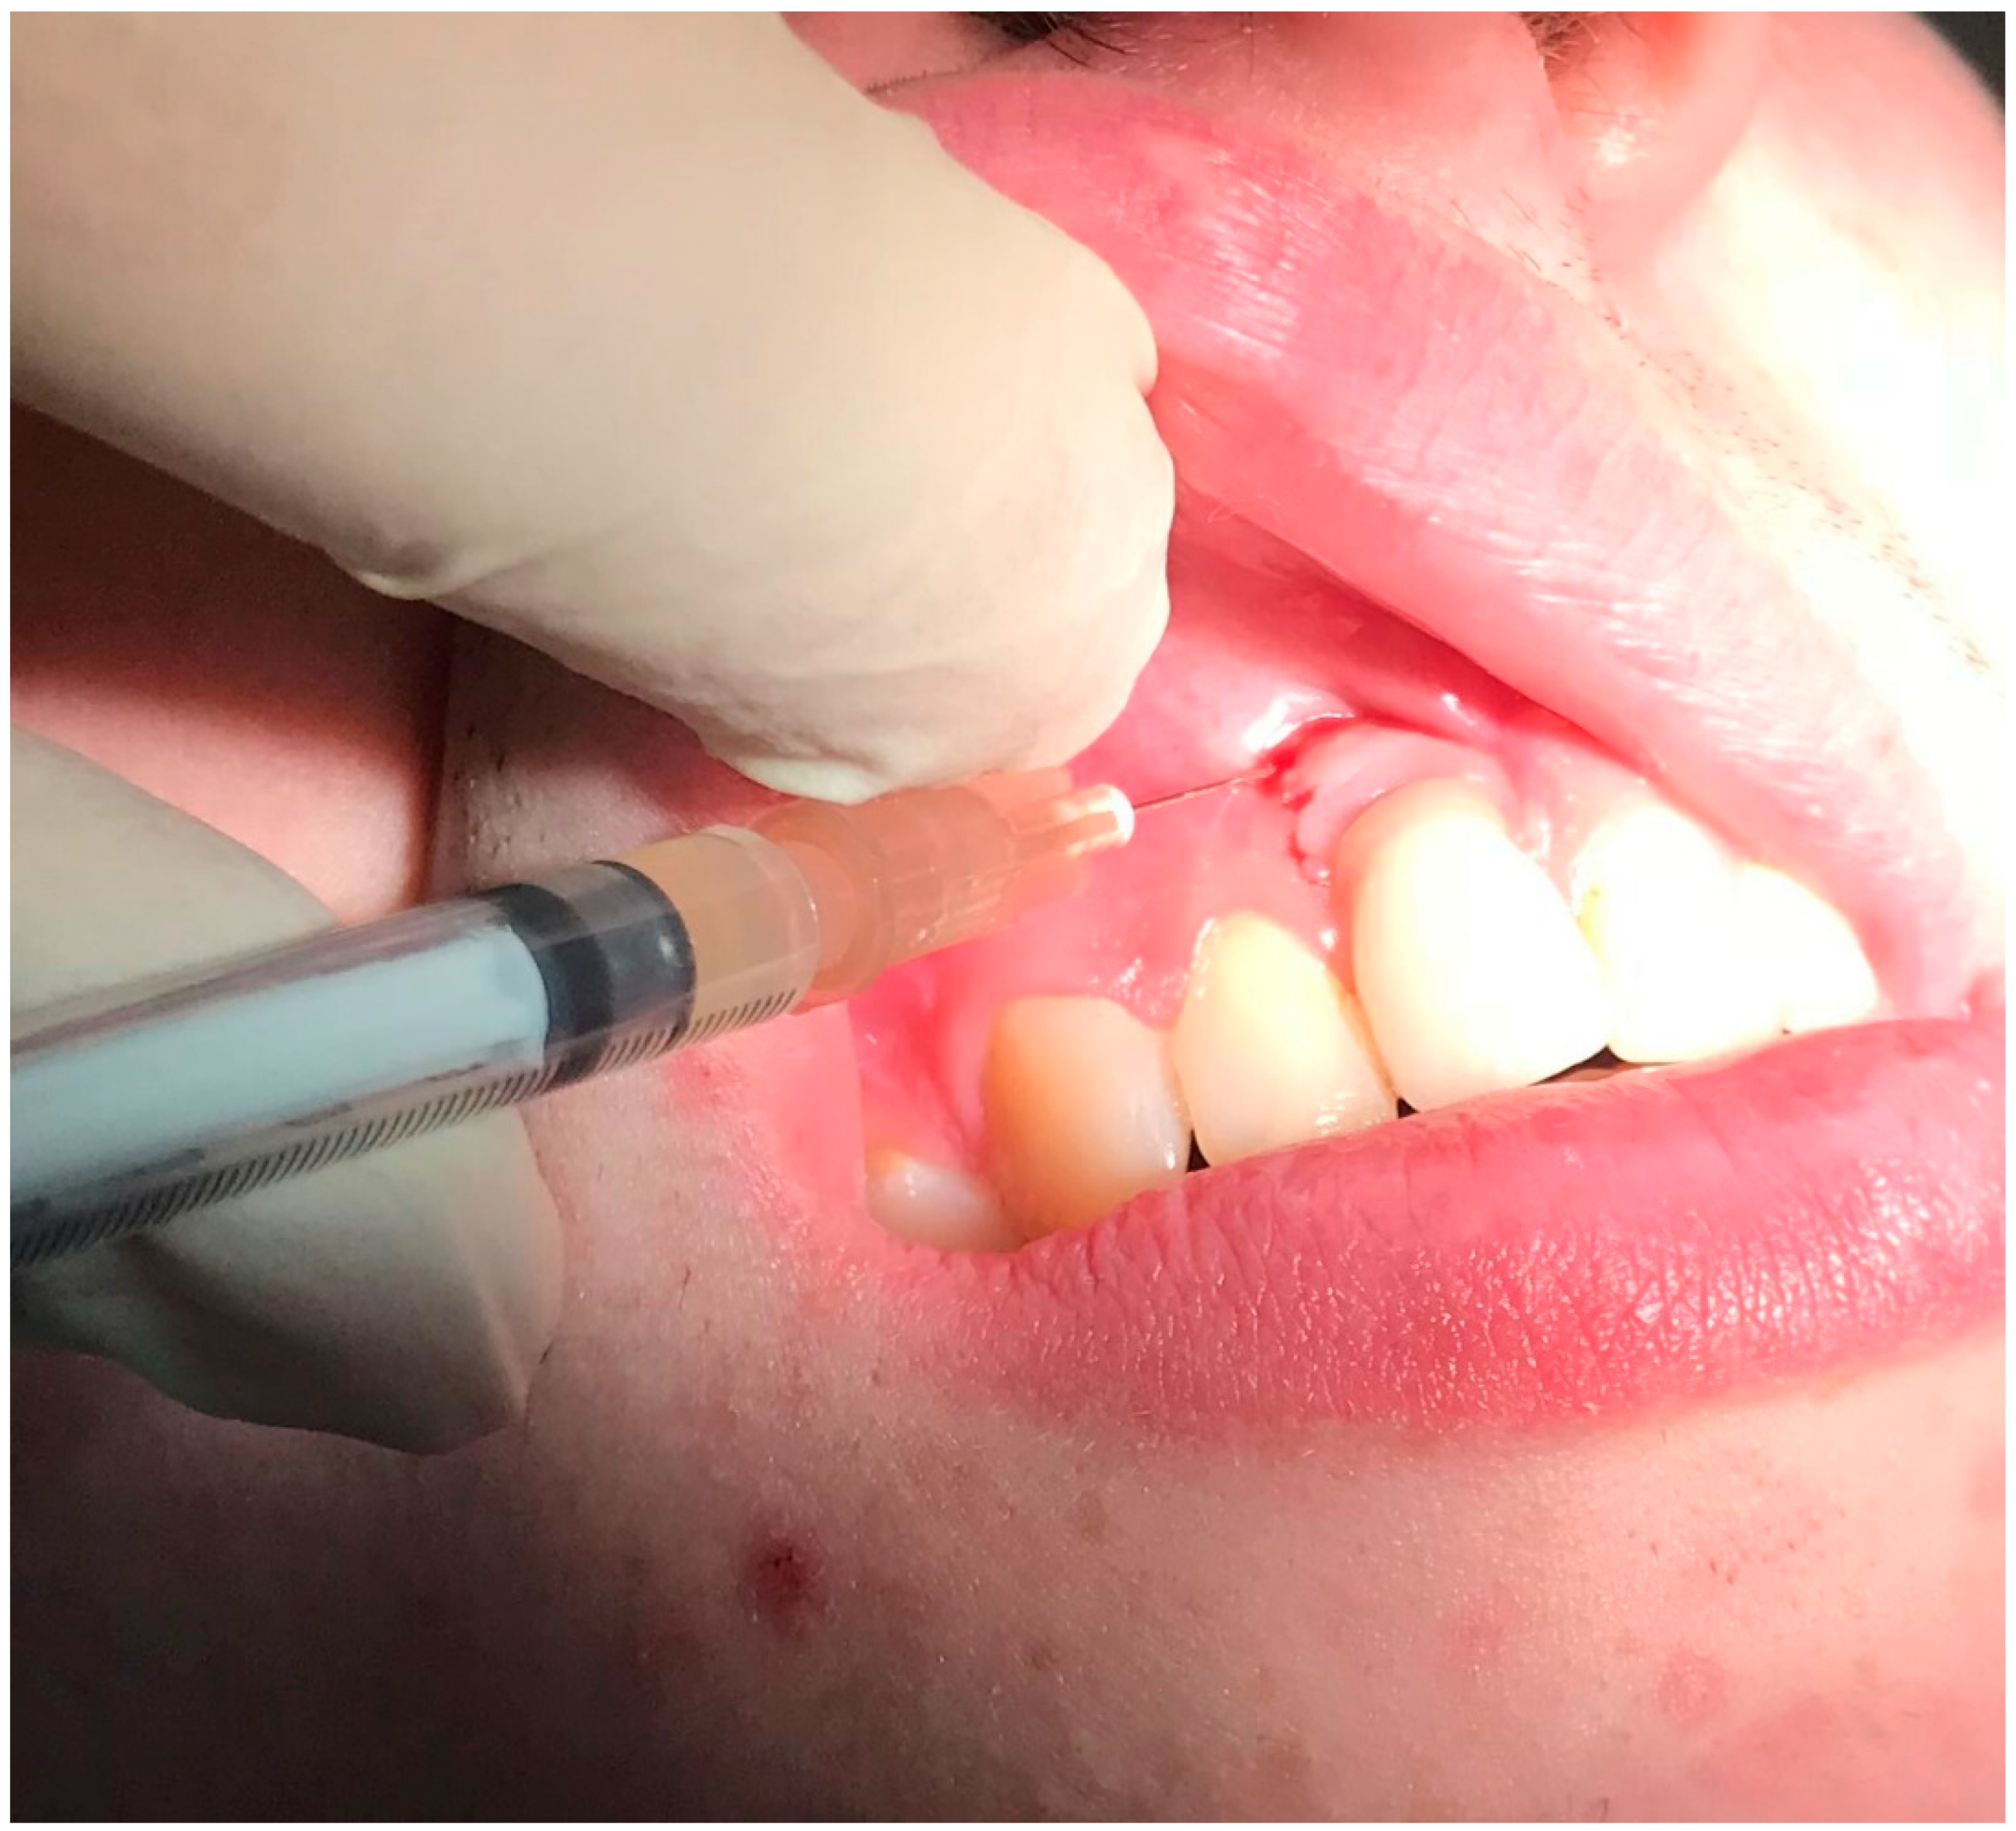

Clinical examination revealed that the patient was rehabilitated through two full-arch fixed prosthesis, each supported by a combination of two axial and two tilted implants placed in the anterior region of maxilla or mandible, following the All-on-4® protocol [15]. Once the prosthesis was removed, the visual aspect of the peri-implant mucosa surrounding implants placed in 3.2 and 4.2 position revealed the presence of local inflammation (with evident redness and swelling), without any evidence of significant tissue retraction. By the use of one plastic probe (Hawe Perio-Probe™, Kerr Corporation, Orange, CA, USA), we found deep (more than 4 mm) probing depth in all sites of 3.2 and 4.2 implants, with extensive bleeding on probing and suppuration (Figure 1 and Figure 2).

Figure 1.

Probing of dental implant area and suppuration in patient during the first visit: (A) in 3.2 position and (B) in 4.2 position.

Before considering performing one surgical procedure in order to treat the pathology (by regenerative or resective surgery), the authors decided to perform nonsurgical treatment, following the patient’s will (who rejected the surgical treatment for the first instance) and to evaluate the results over time, with particular attention to the soft tissue healing following the treatment. We proposed the use of topical applications of 14% doxycycline (Ligosan®, Kulzer, Hanau, Germany). We performed two professional treatments in two visits within 1 week. After local anesthesia with articaine 4% and epinephrine 1:200,000, the antibiotic was placed directly into the pocket with a specific device. The injection was given gently, with a specific and dedicated sterilized device, until we clearly visualized the antibiotic spilling outside of the pocket after filling it completely (Figure 3). After cleaning the surface of the abutments from the residues of the antibiotic, the prosthesis was screwed again. The patient was instructed to avoid any trauma involving the peri-implant mucosa and to rinse with 15 mL 0.2% chlorhexidine twice a day for 7 days after each treatment.

Figure 3.

Application of antibiotics with special device around dental implants in positions 3.2 and 4.2.